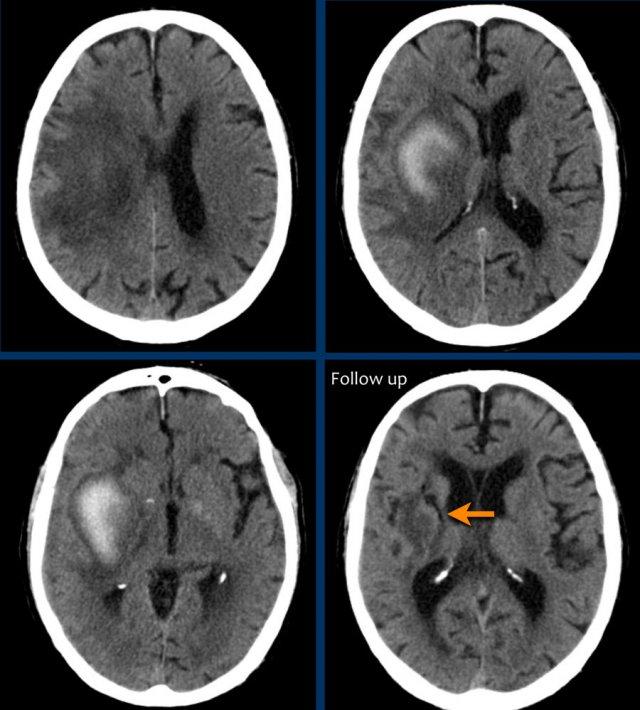

Hạch nền

Xuất huyết tại hạch nền thường gặp trong tăng huyết áp.

Xuất huyết do tăng huyết áp thường xảy ra ở bệnh nhân cao tuổi và thường ở vị trí trung tâm.

Điều này giúp phân biệt xuất huyết do tăng huyết áp với xuất huyết ở bệnh nhân mắc bệnh lý mạch máu não dạng bột (CAA) – vốn có vị trí ngoại vi hơn, mặc dù có thể có sự chồng lấp.

Các hình ảnh cho thấy xuất huyết do tăng huyết áp điển hình tại nhân bèo (putamen), là phần lớn nhất và nằm ngoài cùng của hạch nền.

Tiếp tục xem các hình ảnh theo dõi…

Trên phim chụp theo dõi, chỉ thấy mất nhu mô tại nhân bèo – nơi xuất huyết đã xảy ra (mũi tên).

Ba hình ảnh đầu tiên cho thấy khối tụ máu lớn tại hạch nền bên phải kèm phù não lan rộng.

Hình ảnh theo dõi một năm sau cho thấy hình ảnh hang hóa dạng tuyến tính do mất mô (mũi tên) và giảm tỷ trọng hạch nền là hậu quả của xơ hóa thần kinh đệm (gliosis).